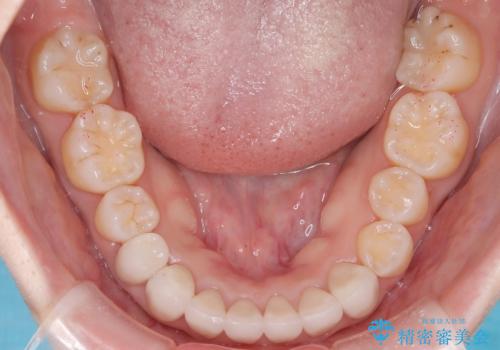

【オールセラミック】下の前歯が痛い。

- 以前に治療した前歯が痛むことを主訴に来院されました。

根っこに病気があり、根管治療から被せ物まで治療を行いました。

根管治療を行った後、3ヶ月間治癒の確認をしてからオールセラミックスペシャルで治療を行いました。